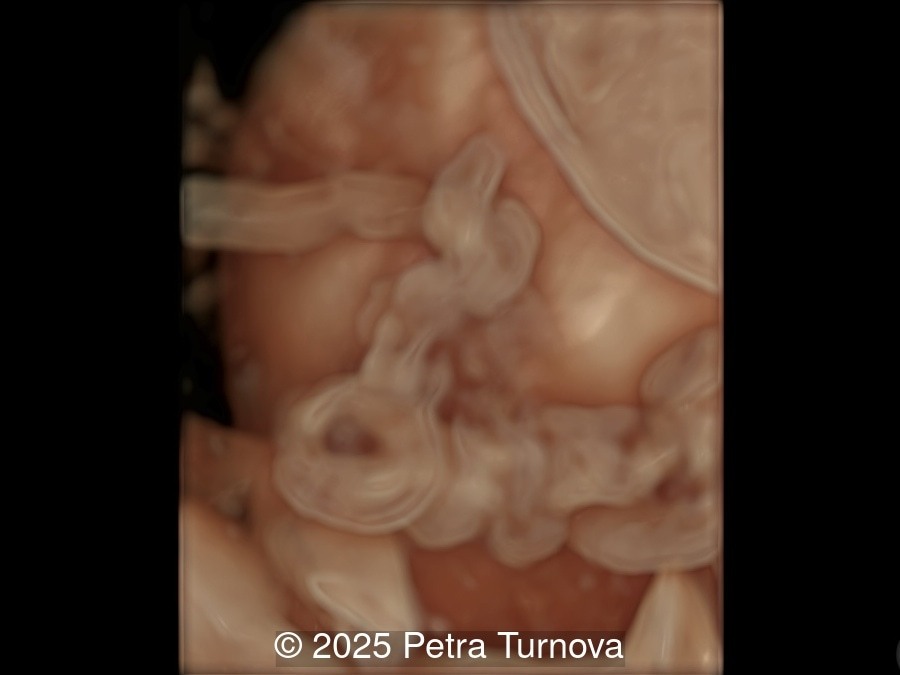

We present a case of cord entanglement. Unfortunately, the pregnancy ended in fetal demise two weeks after our exam.

Monochorionic monoamniotic pregnancy represents the rarest type of multiple gestation, accounting for approximately 1% of all twin pregnancies. The risk of fetal mortality in this type of pregnancy is around 80%. In the case of twin pregnancies, the fetuses share a common placenta, amnion, and chorion. The chorionicity and amnionicity are determined by the timing of zygote division. If the zygote divides between days 8 and 12, a monochorionic monoamniotic pregnancy results. A specific complication uniquely associated with monoamniotic and monochorionic pregnancy includes conjoined twins and cord entanglement.

Cord entanglement can be visualized from the 12-13 weeks of pregnancy. The risk of cord events increases in cases of close cord insertion on the placenta. Some studies have confirmed that intermittent occlusion is associated with neurological morbidity, while prolonged occlusion is fatal. Ultrasound may visualize intertwined umbilical cords. On Doppler flow studies, intermittent or persistent notching of the umbilical artery may be present. This phenomenon is typically observed in abnormal uterine artery flow associated with placental insufficiency and is less frequently seen in umbilical artery flow disorders. Based on physical calculations, it has been shown that notching does not occur unless there is a reduction in tube diameter below 75%. Therefore, notching is present in cases of significant flow reduction.